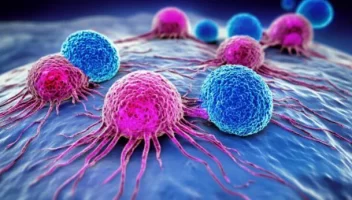

ما هو العلاج المناعي

→ العودة لدليل السرطان العلاج المناعي: إيقاظ “الجيش الداخلي” لمحاربة السرطان أقوى سلاح ضد المرض موجود داخل جسمك بالفعل. تعرف على الطريقة الثورية التي تدرب جهازك المناعي ليصبح هو العلاج. ما هو العلاج المناعي (Immunotherapy)؟ على عكس الكيماوي (الذي يهاجم السرطان من الخارج) أو العلاج الموجه (الذي يقطع إمداداته)، العلاج المناعي لا يلمس الورم مباشرة! […]